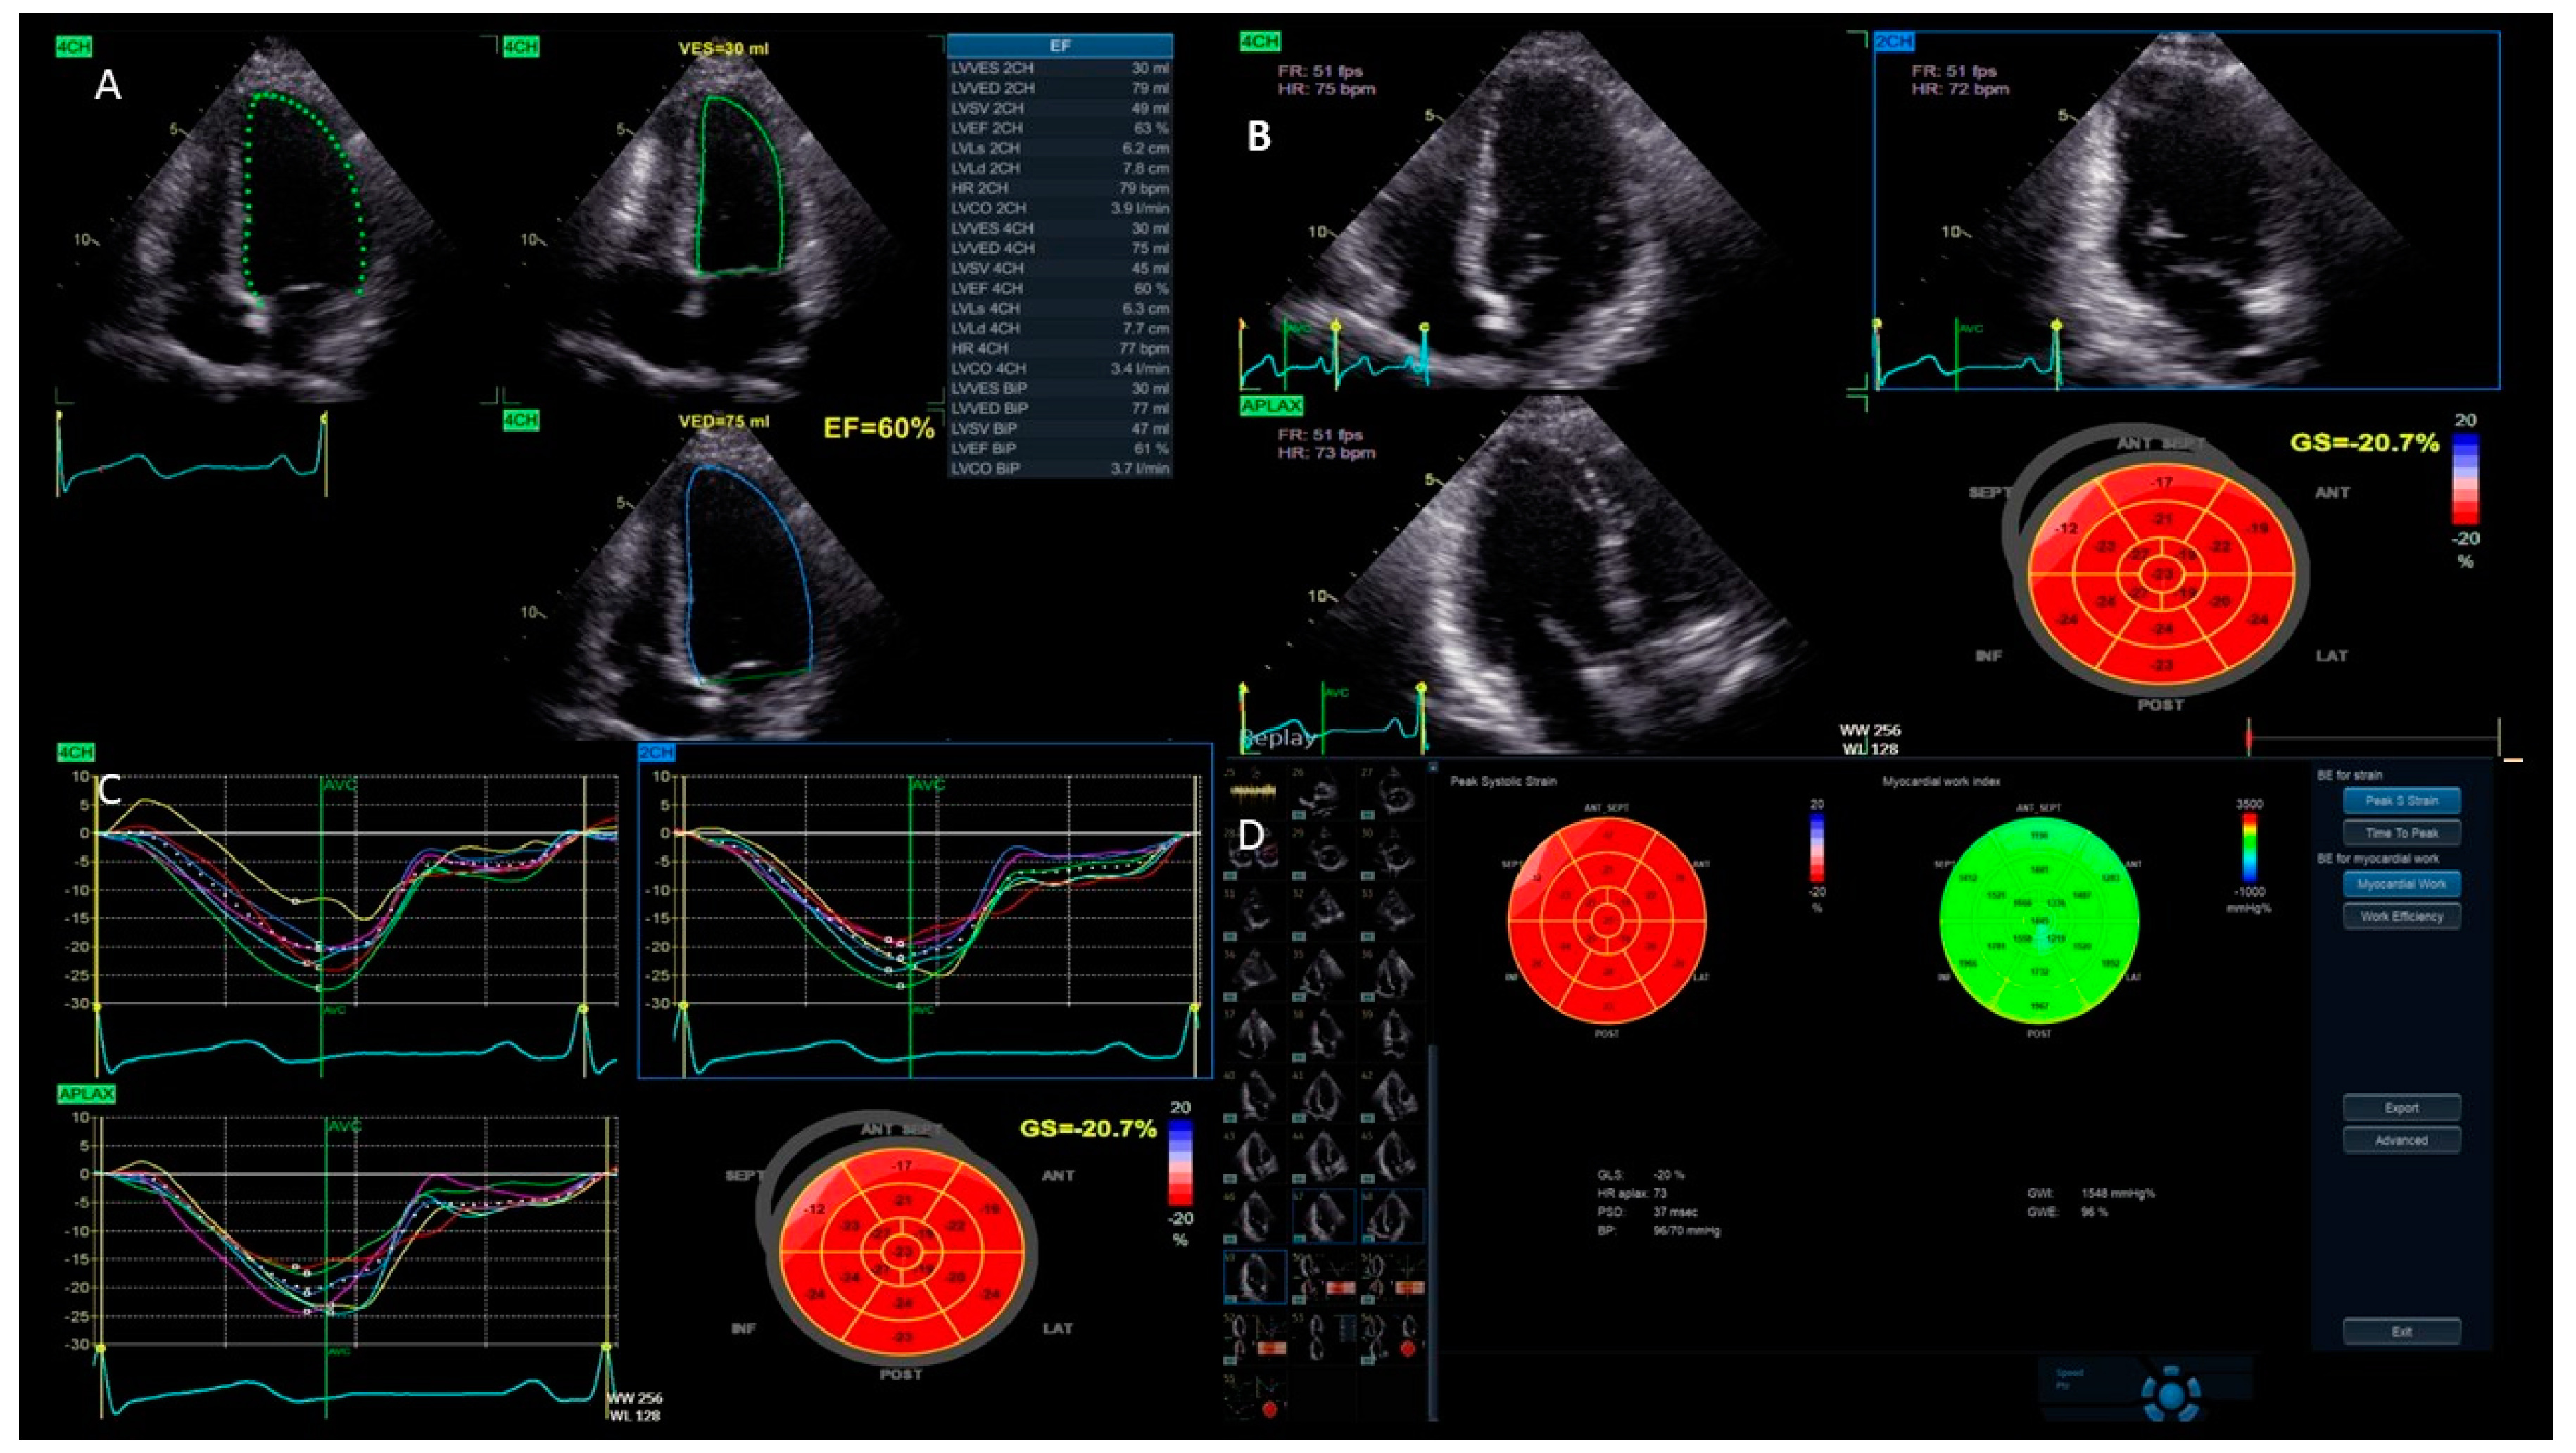

- Left ventricular function: This technology allows for a more accurate evaluation of the left ventricle (LV) function, avoiding geometric assumptions regarding the LV shape. It provides faster, more accurate, and reproducible measurements of ventricular volumes, compared to traditional 2DE (Figure 1).

- Left ventricular function: One of the main uses of strain imaging is to detect early subclinical myocardial dysfunction. For instance, in patients undergoing chemotherapy, strain imaging can detect early signs of heart damage before a significant reduction in the LVEF occurs. This allows for prompt intervention and adjustments to the cancer treatment to prevent further harm to the myocardium [17,18]. The current definitions of cancer therapy-related cardiac dysfunction primarily rely on a reduction in the LVEF and/or a relative decrease in the GLS beyond a specific threshold [19]. As a result, baseline cardiac assessments are recommended for all patients prior to initiating cardiotoxic cancer treatments. GLS assessment using speckle tracking, particularly from three apical views, is strongly advised at the baseline, especially for patients at a moderate-to-high risk. It is important to acknowledge that strain measurements may vary between different vendors. Therefore, to ensure consistency, serial GLS evaluations for each patient should be conducted using the same equipment and software. A median GLS reduction of 13.6% has been identified as a predictor of future LVEF decline, with an upper limit of 15% recommended as the threshold for GLS reduction during cancer therapy to enhance specificity [19,20]. These measurements help stratify the risk of cancer treatment-related cardiovascular toxicity and identify significant changes during therapy. Notably, a normal LVEF does not exclude the presence of cancer treatment-related cardiac dysfunction; GLS, instead, can reliably detect early systolic impairment. For instance, Muckiene et al. demonstrated that a reduction in GLS is significantly linked to early anthracycline-induced cardiotoxicity in patients undergoing anthracycline-based chemotherapy. This finding suggests that GLS could potentially serve as a predictor for any subsequent declines in the LVEF associated with this chemotherapy regimen [21]. In the assessment of ischemic heart disease, strain imaging provides valuable information about regional myocardial function [16]. During an ischemic event, specific areas of the myocardium may show reduced strain, indicating impaired contractility. This technique can help identify a viable but hibernating myocardium, which can benefit from revascularization procedures. Strain imaging is also useful in evaluating the effectiveness of reperfusion therapies following acute myocardial infarction by assessing the recovery of myocardial function in the affected regions [22,23,24]. Furthermore, the management of HF patients benefits significantly from strain imaging. It offers a more sensitive measure of myocardial function compared to traditional echocardiographic parameters (Figure 4). GLS has been shown to correlate better with outcomes in heart failure patients, providing prognostic information that aids in clinical decision-making. In patients with HF with mildly reduced ejection fraction (HFmrEF), strain imaging can uncover subtle myocardial dysfunction that is often missed by conventional measures. Chang et al. demonstrated that in patients with HFmrEF, a LV GLS cut-off value of −11% effectively differentiated the subsequent risk of cardiovascular death [25]. This enhances the understanding and management of this complex condition [26].